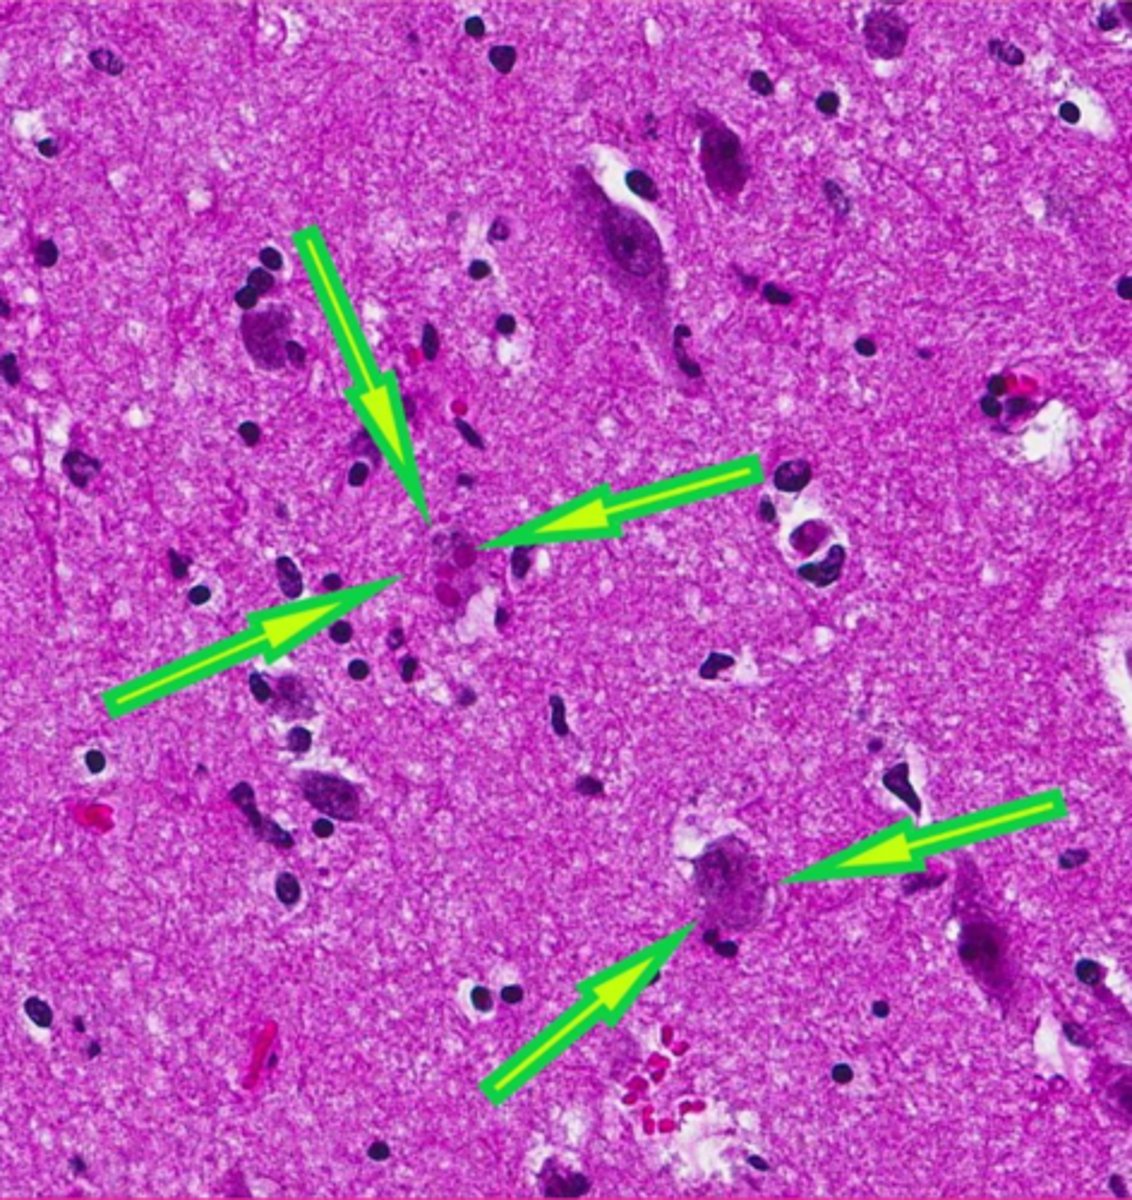

Rabies, canine distemper

what two RNA virus inclusions were we given as examples?

negri bodies

rabies inclusions are called?

rabies

which viral inclusion?

canine distemper virus

which viral inclusions?